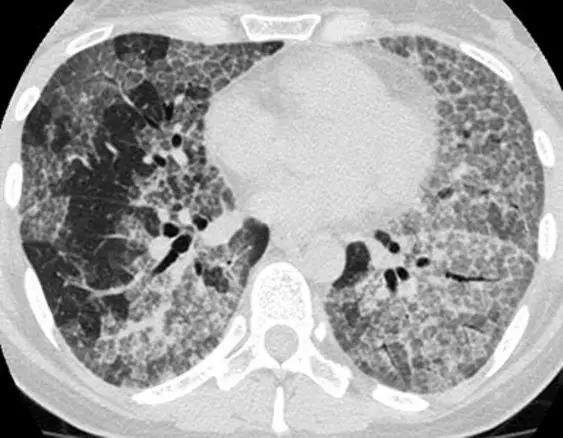

5、磨玻璃影-网状影混杂模式

有时,在肺部同一区域中可能同时存在磨玻璃样影和网状影共存,这种组合几乎等同于不可逆的纤维化。典型疾病:是非特异性间质性肺炎(NSIP)。表现为磨玻璃影改变为主、轻度网状改变。鉴别疾病:硬皮病、特发性肺纤维化(IPF)和脱屑性间质性肺炎(DIP)。

特发性肺纤维化(IPF)有时可能与NSIP难以区分,HRCT在区分IPF和NSIP方面的特异性范围为63%至70%。有利于IPF的鉴别诊断是呈现显著的网状蜂窝样改变,少许毛玻璃改变。

*IPF HRCT在肺底水平上表现出混合的“磨玻璃样和网状图案”,其特征是磨玻璃样改变的区域内可见牵引性支气管扩张和支气管扩张。少许蜂窝样改变。